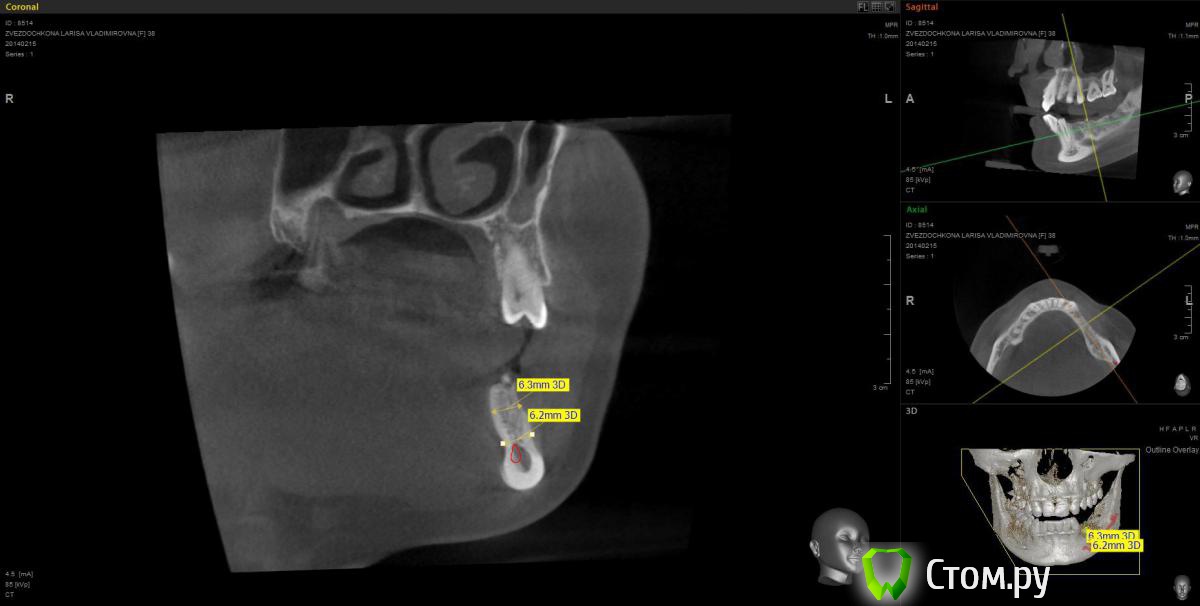

mapmax Опубликовано 3 марта, 2014 Поделиться Опубликовано 3 марта, 2014 Итак,коллеги,нуждаюсь в Вашем совете. У пациентки концевой дефект в обл 34 35 36 37, в периапикальной обл. 34 был воспалительный процесс который обострился и осенью прошлого года зуб был удален(не мной). Сейчас стоим перед имплантацией. Я рекомендую ставить импланты в обл отсутствующих зубов,но по финансовым соображениям пациентка настаивает на операции в обл 34 35 и позже в обл 36 37. Система выбрана Штрауманн SP SLActiv. Из за особенностей формы альвеолярного отростка в обл. 34 35( S-образная) и недавнего удаления 34 я рассматриваю установку импланта с язычным наклоном размера 4.8х10 RN в обл 35 RN 4.8х12. Но есть опасность оголения витков с вестибулярной стороны.Может все же сперва провести аугментацию "Аллопластом" с мембраной с вестибулярной стороны и отсрочено имплантация?! Срезы ДКТ прилагаю. Спасибо. Ссылка на комментарий